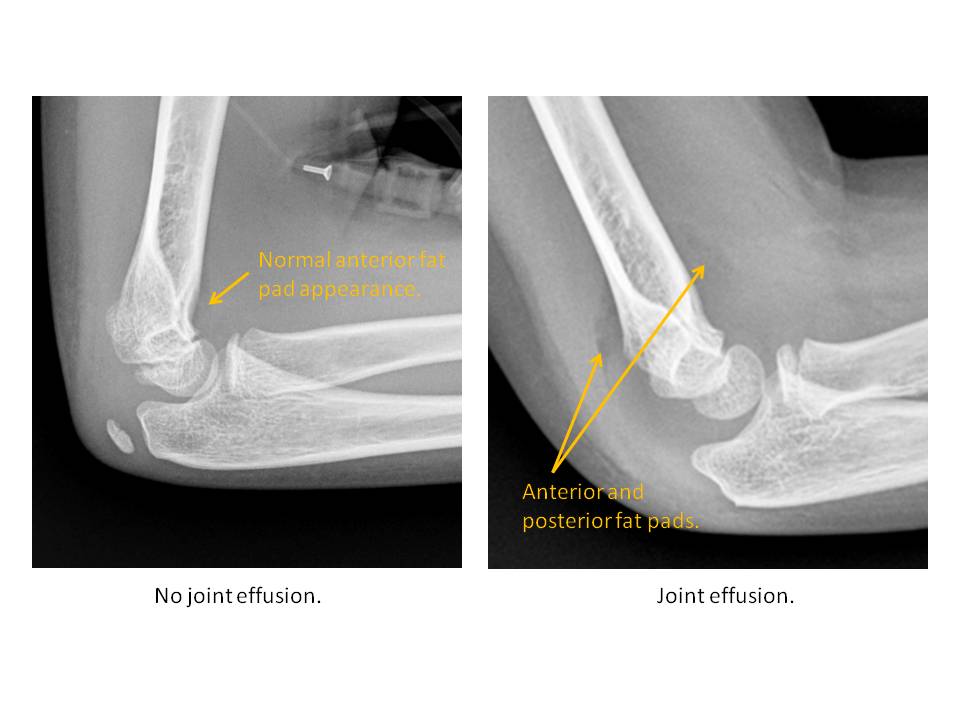

A joint effusion is present. |

Yes | NA |